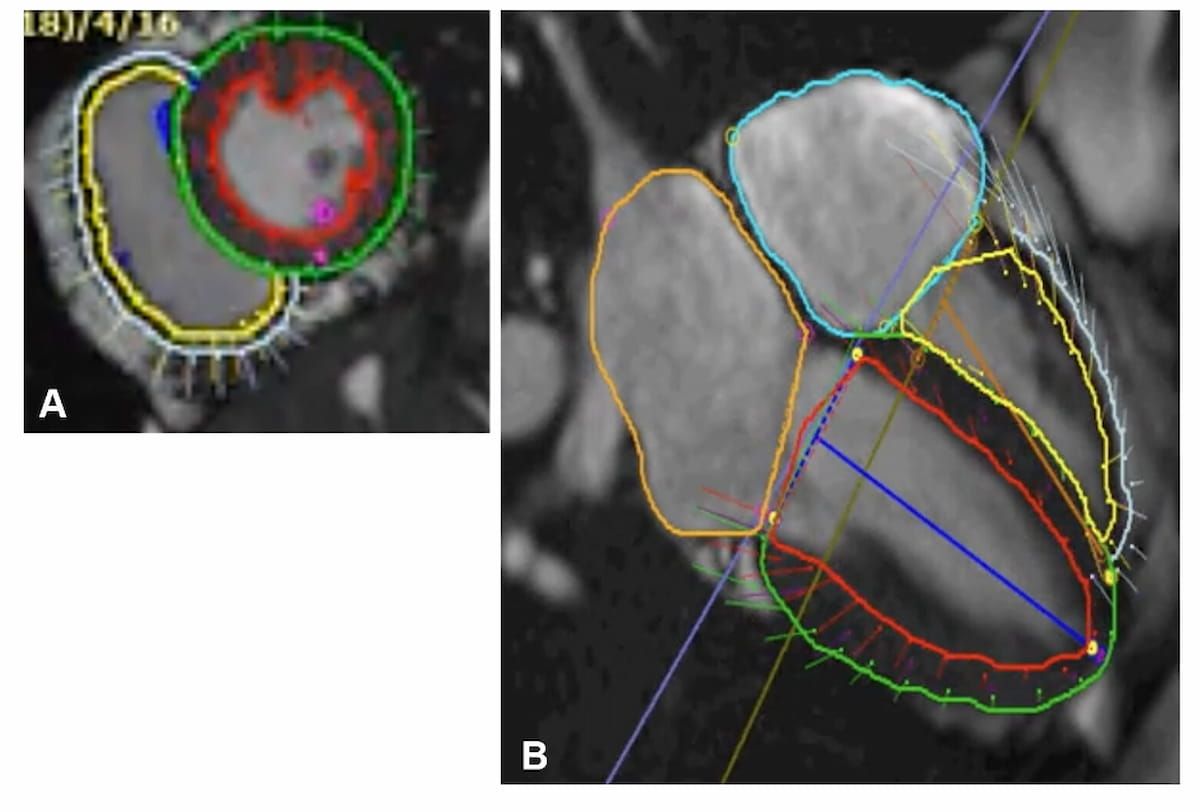

Incorporating mpMRI radiomics, clinical characteristics, deep learning and pathomic features, a multimodal model offered 82 percent and 87 percent AUCs for predicting overall survival outcomes at five years and seven years, respectively, for women treated with neoadjuvant chemotherapy for breast cancer.